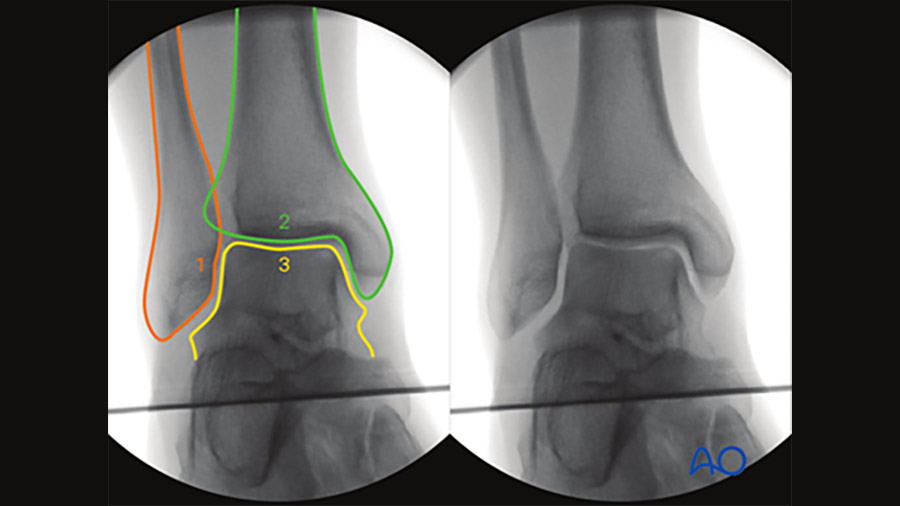

- Ankle (malleoli)